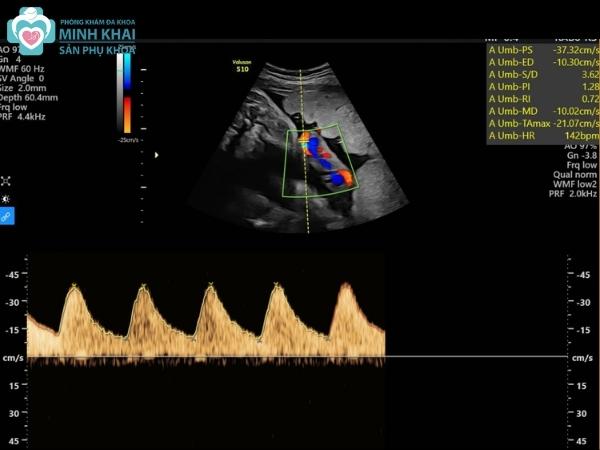

Với mức giá siêu âm 5D khá cao thì liệu siêu âm 5D có chính xác không? Siêu âm thai 5D là kỹ thuật siêu âm chuẩn xác hàng đầu hiện nay. Nó kết hợp điểm vượt trội của hình ảnh siêu âm màu 4 chiều với phương pháp đo nhịp tim thai Doppler. Ưu điểm đó giúp sản phụ có thể theo dõi hình thái thai nhi chi tiết cũng như thấy rõ hoạt động, biểu cảm đa dạng của bé con.

Bên cạnh đó, siêu âm màu 5D hỗ trợ bác sĩ chẩn đoán và nắm bắt được kịp thời các thông số quan trọng về hệ tuần hoàn máu, đường tiết niệu, nhau thai, nước ối,... chính xác đến 85% đến 95%. Nhờ vậy, việc chẩn đoán sớm các dị tật bẩm sinh, bất thường của thai nhi sẽ dễ dàng hơn ngay từ thời gian đầu mẹ mang thai.

Siêu âm 5D tim thai

Hình ảnh siêu âm 5D có ứng dụng quan trọng trong việc siêu âm tim thai. Siêu âm màu 5D cung cấp hình ảnh khảo sát và trình bày cấu trúc tim thai nhi trên 9 mặt cắt cơ bản. Nó giúp theo dõi chi tiết từng nhịp cử động của buồng tim, mạch máu, lá van. Nhờ vậy, bác sĩ có thể đánh giá được sự hoạt động bình thường của tim thai cũng như phát hiện dấu hiệu bệnh tim bẩm sinh nếu có.